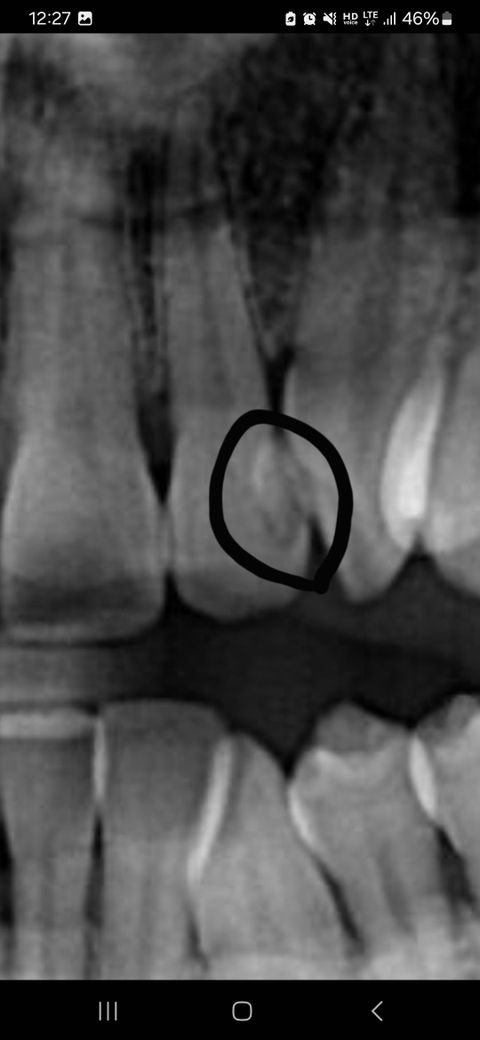

레진으로 떼운 곳에 색깔변화 의미 궁금합니다

동그라미 표시가 수년전 충치를 레진으로 떼운건데

색상보니 혹시 다시 충치가 생기는건지

아니면 이상없는건지 알고싶습니다

x-ray 사진만으로는 새로운 충치 생겼는지 확인하기 어렵습니다. 레진 떼운 부위는 x-ray 상에서 색깔이 다르게 나타납니다. 치과에서 육안 검사하는 것이 우선입니다.

다시 충치가 생겼을 수도 있어보입니다. 위 사진 하나만으로 판별하긴 어려우니 치과 가보시는 게 좋겠습니다.

엑스레이 상으로 저렇게 보이는 경우는 안쪽에 레진이 꽉 안찬경우나 본딩제가 엑스레이 상으로 보이는경우가 있습니다.

레진으로 떼운 건 조금씩 마모되어서 틈이 생기거나 아니면 처음부터 해당 부위가 말끔히 채워지지 않았을 수도 있습니다.